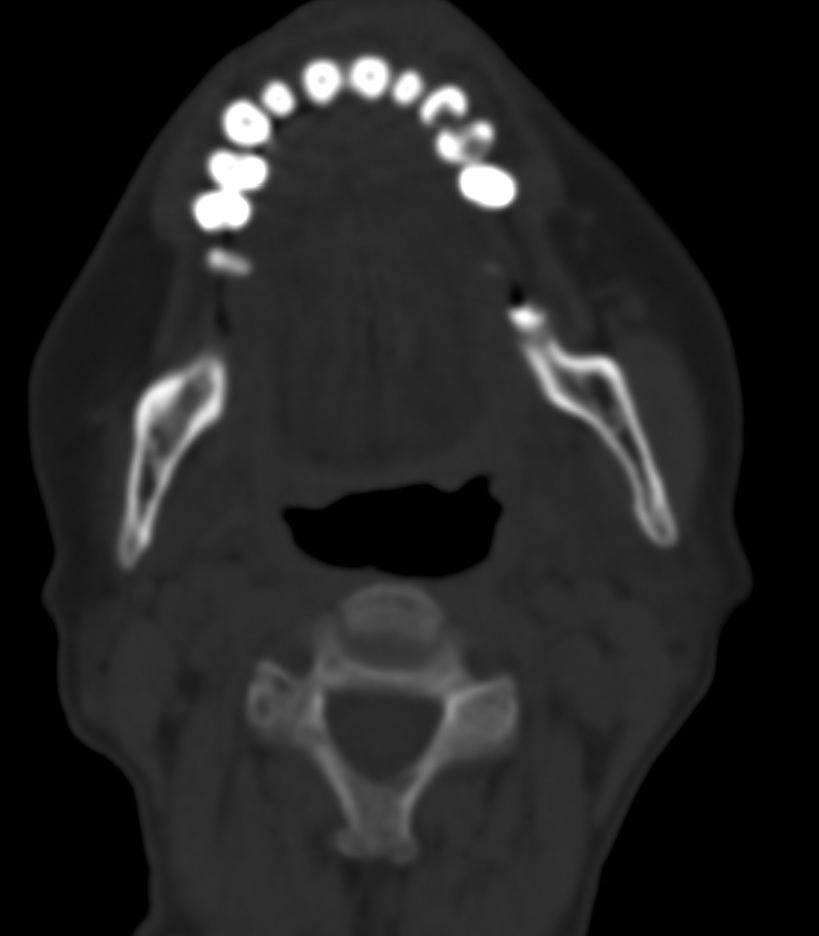

女,68岁。发现上唇无痛性肿块2年多,查体局部皮肤隆起,其余未见异常。

病灶ct值约42hu。

病理结果:唾液腺混合瘤。

上唇唾液腺混合瘤,罕见!学习了!